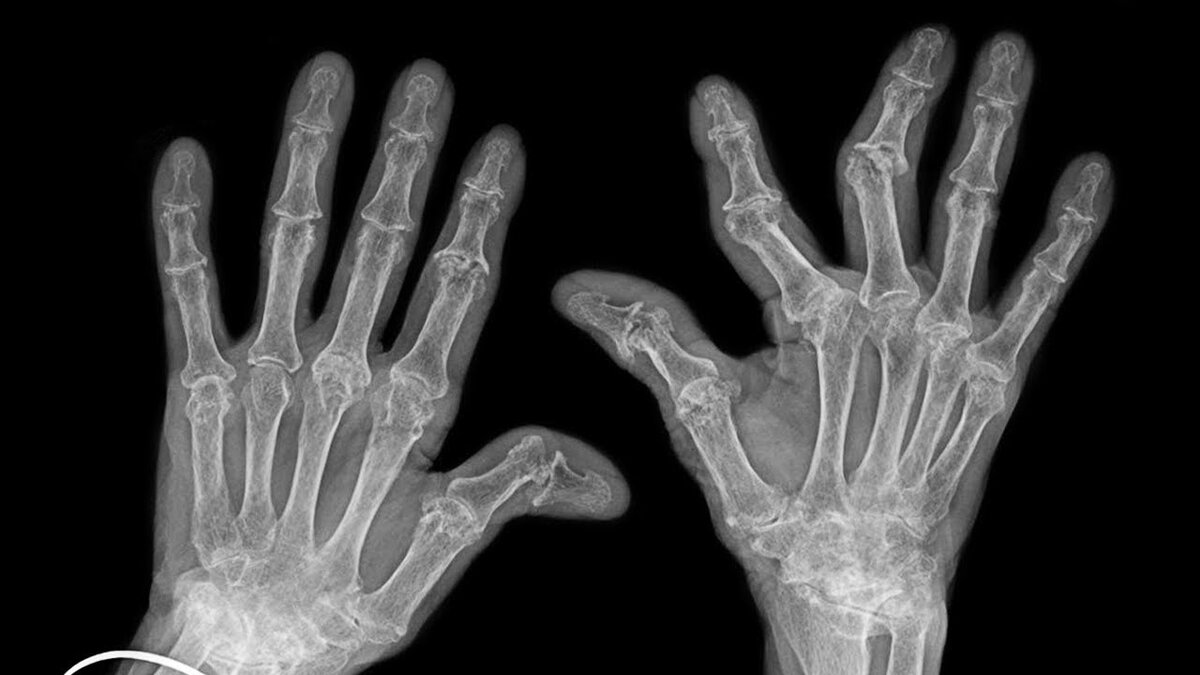

На протяжении 10 лет он хрусте пальцами только на одной руке, потом сделал рентген и не обнаружил никаких изменений в суставах.